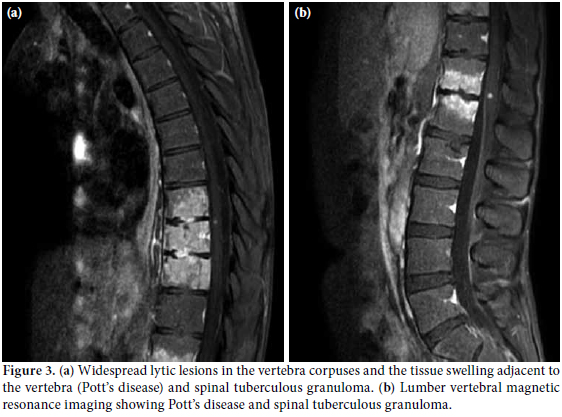

A 22-year-old male patient was presented to the emergency room of our hospital with complaints of fever, headache, and fatigue which had been occurring for 10 days. The medical history revealed that he had been diagnosed as having Behçet’s disease in 2007 and had been using prednisolone since the time of diagnosis. The dosage of prednisolone was increased up to 64 mg/day by the supervising clinician. Cyclosporine-A had been added to the treatment at 100 mg/day two months previously due to eye involvement but was discontinued after one week due to side effects of fever, fatigue, and headache. The patient was prescribed azathioprine at 100 mg/day on the follow-up visit, and he had been using this drug for nearly 10 days prior to being admitted to our hospital. The physical examination findings revealed a body temperature of 39.8 °C, arterial blood pressure of 110/70 mmHg, and a heart rate of 112/per minute. Neck stiffness was minimally positive. He had swelling and sensitivity on palpation in the right scrotal region that had started three months earlier. Laboratory examinations were as follows: leukocyte count 7.400/mm3, erythrocyte sedimentation rate 87 mm/h, C-reactive protein: 13.4 mg/dl in cerebrospinal fluid (CSF) analysis, leukocyte count: 20/mm3, protein: 200 mg/dL, and glucose: 27 mg/dL (blood glucose: 94 mg/dL). There was no growth on the CSF culture. A chest X-ray was normal. Since the CSF findings and physical examination results could not rule out bacterial meningitis, he was started on ceftriaxone 2x2 gr intravenously. He had no regression of complaints in the first week of treatment, and his antibiotic treatment was discontinued. Internal disease and neurology consultations in conjunction with the clinical findings and CSF results led to a diagnosis of neuro-Behçet’s disease. Scrotal ultrasound screening was consistent with epididymitis. A large number of leukocytes were observed in the material aspirated from the testis (90% lymphocyte in nature). Ehrlich- Ziehl-Neelsen (EZN) staining detected acid-resistant bacteria. Treatment with isoniazid, ethambutol, pyrazinamide, and rifampicin was initiated under the diagnosis of testis tuberculosis. Subsequently, chest high resolution computed tomography (HRCT) and brain magnetic resonance imaging (MRI) were done. The chest HRCT result was consistent with miliary tuberculosis (Figure 1), and the brain MRI revealed findings were consistent with tuberculous granuloma and tuberculous meningitis (Figure 2). The vertebral MRI showed that widespread lytic lesions in the vertebra corpuses and the tissue swelling adjacent to the vertebra were consistent with Pott’s disease and spinal granuloma (Figure 3a and 3b). Based on these examinations, the patient was considered to have disseminated tuberculosis (testicular tuberculosis, miliary tuberculosis, tuberculosis meningitis, spinal granuloma, and Pott’s disease). The anti-tuberculous treatment was revised with the ethambutol being replaced by streptomycin. The patient’s body temperature returned to normal on the eighth day of treatment. The patient, whose general condition was observed to improve, is still receiving the treatment.